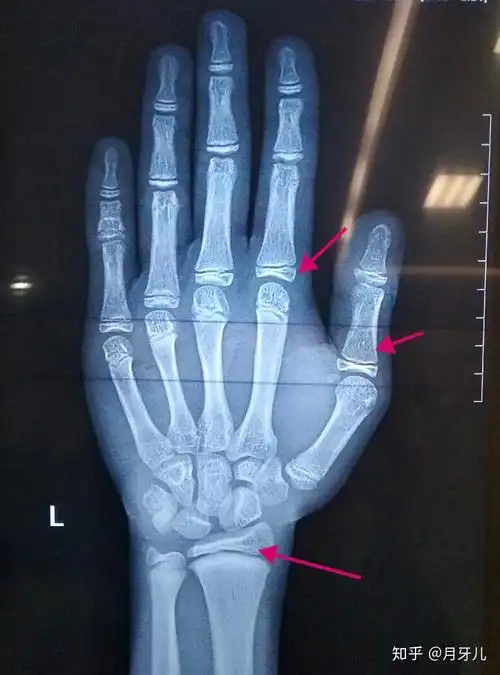

骨骺线算闭合了吗?

骨骺基本闭合,最多还有1cm的生长空间.可是目前身高只有163.5cm!

今天去拍了手骨的片子看看骨骺线闭合没,还能长多高,懂的人给我看看吧

骨骺线接近闭合这么看?